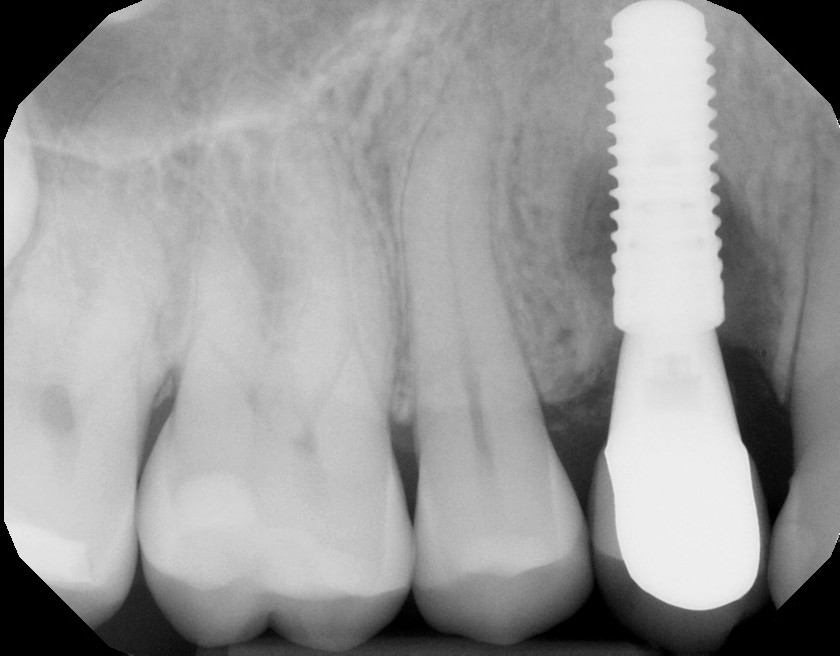

This mouth had recession on just one tooth with very little bone to support the tooth. The area needed support and thickness. The tissue was placed and the area now has thicker tissue to withstand the forces that the patient needs to place on it.